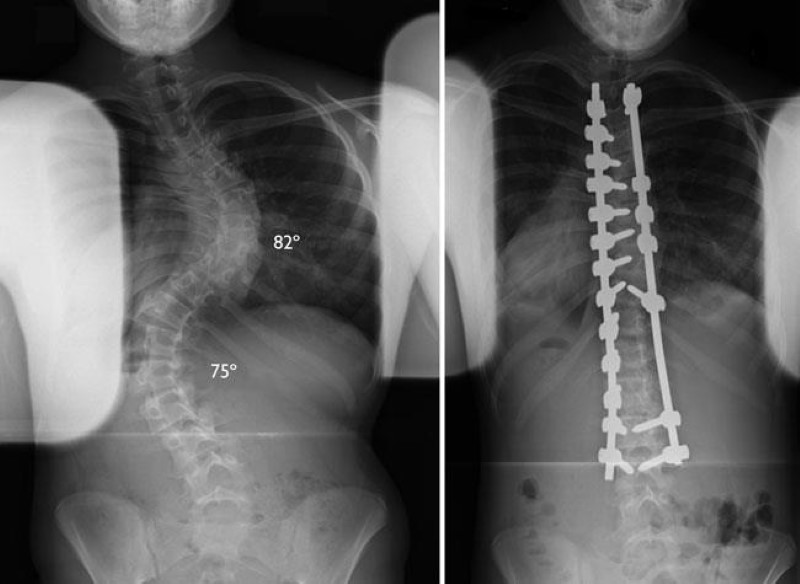

x-rays of scoliosis curves and fusion

(Left) This X-ray shows two large curves that require surgery. (Right) The same patient after surgery to correct the curves.

Courtesy of Texas Scottish Rite Hospital for Children